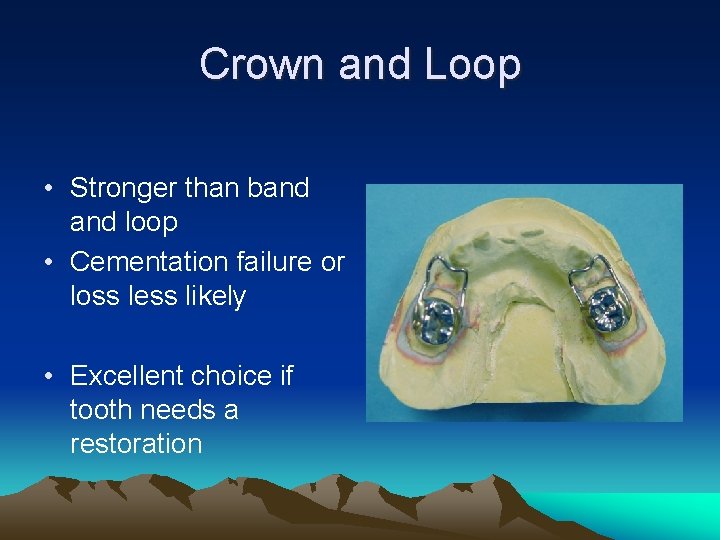

Crown and Loop • Stronger than band loop • Cementation failure or loss less likely • Excellent choice if tooth needs a restoration